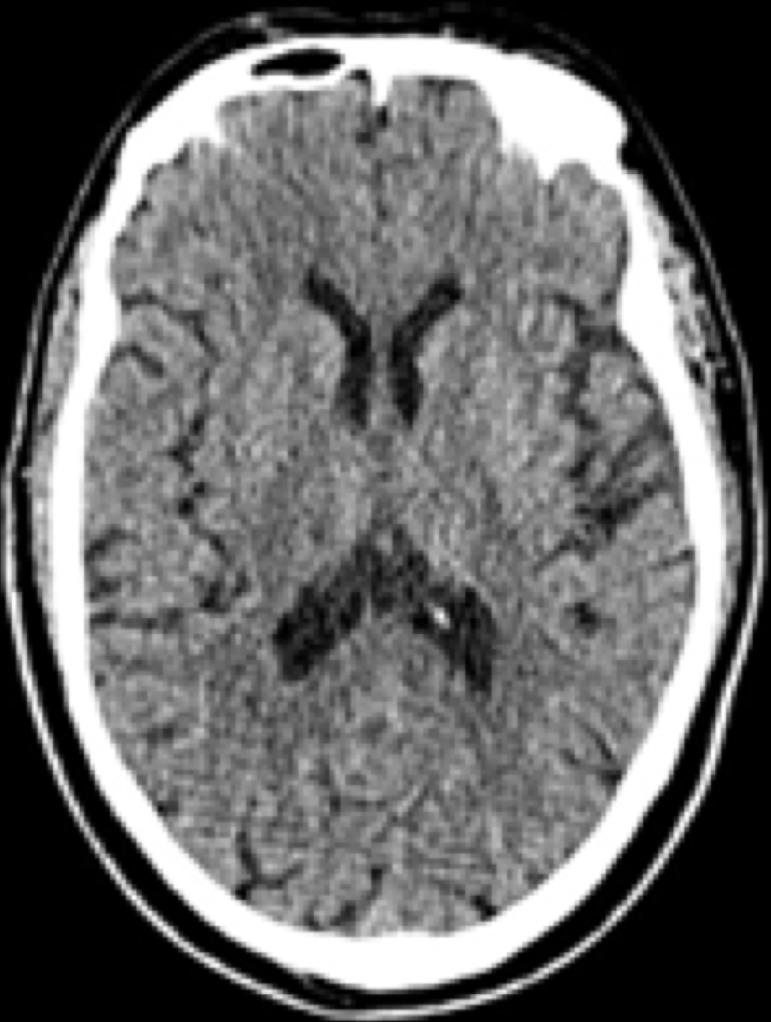

Case summary: A 77-year-old male with diabetes mellitus and CKD stage 3 underwent elective right total knee arthroplasty for grade 4 osteoarthritis under spinal anesthesia. Preoperative evaluation revealed deranged renal function tests but no other significant abnormalities. Postoperative pain was managed with multimodal analgesics, including intravenous tramadol and a buprenorphine skin patch. On postoperative third day, the patient was found unconscious (Glasgow Coma Scale 8/15) with mild respiratory depression. Investigations ruled out stroke, pulmonary embolism, or other cardiopulmonary events. Elevated serum tramadol levels suggested opioid toxicity exacerbated by impaired renal clearance. The buprenorphine patch was removed, and diuresis was initiated. Supportive management, including prophylactic intubation, led to recovery of consciousness within 48 hours, and the patient was extubated and mobilized by postoperative sixth day. Pain control was maintained with oral paracetamol and pregabalin. The patient was discharged on postoperative tenth day in stable condition with improved pain scores and mobility. This case underscores the need for cautious use of tramadol in elderly patients with CKD due to impaired drug clearance and the potential for toxicity. It highlights the importance of close monitoring, judicious analgesic use, and prompt management of complications to ensure favorable postoperative outcomes in high-risk populations.